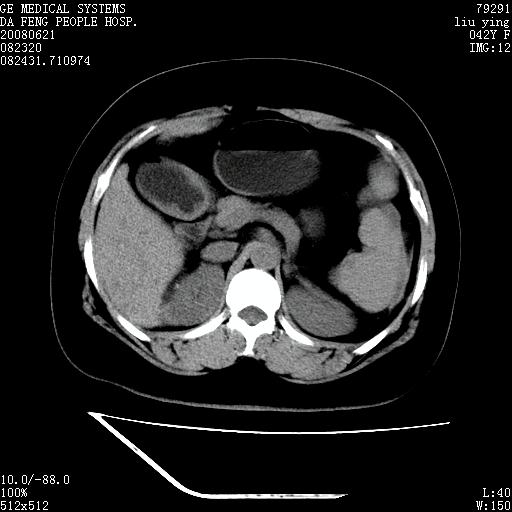

标题: CT14225:女性46岁。当地B超示肝内占位,来我院作CT检查。请 [打印本页]

标题: CT14225:女性46岁。当地B超示肝内占位,来我院作CT检查。请

速升速降,支持肝癌.脾体积增大,形态欠规整,请询问病史是否做过脾动脉栓塞.

速升速降,支持肝癌可能。

快进快出,符合肝癌表现-----------

肝内结节强化特点符合原发性肝癌表现,脾脏改变考虑为增大及先天发育所致。

动脉期病原灶明显强化高于肝密度且中央有无强化区,静脉期强化程度下降明显,延迟低于肝密度,考虑肝腺瘤可能性大,

肝内结节强化特点:快进快出符合原发性肝癌表现

此患者虽然符合快进的特点,却不符合快出的特点,因为门脉期几乎是等密度,不符合肝癌的增强表现,所以我考虑肝局灶性结节增生可能性大